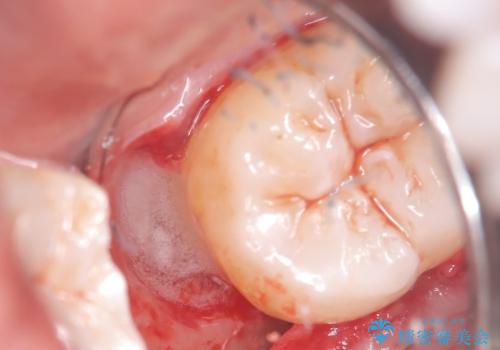

遠心から舌側、唇側に及ぶ深い垂直的骨欠損も認めたため、歯科衛生士による歯周基本治療の後、歯周外科(再生療法)を行いました。

レントゲン写真は、処置後一年経過時のもので、歯周ポケットは遠心4mm、舌側3mmまで減少、出血なし。